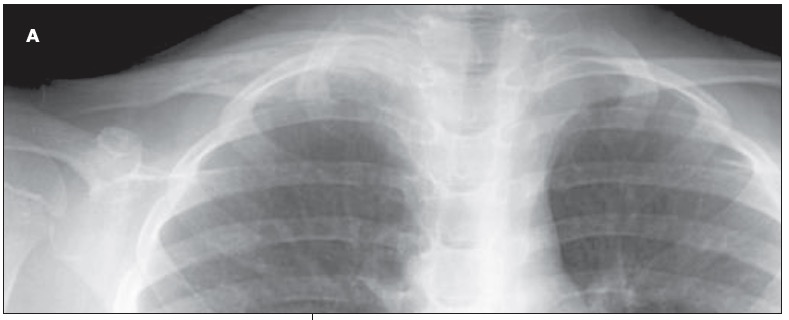

ABSTRACT: Most musculoskeletal infections in children result from hematogenous inoculation. Infections vary greatly in severity and complexity. Sequential determination of the C-reactive protein level may be the most important laboratory test in determining response to treatment. High-quality plain radiographs are essential. Ultrasonography, technetium 99m-diphosphonate scanning, and MRI also are used. In acute osteomyelitis, focal bone pain usually is accompanied by fever or malaise; antibiotic therapy is indicated. Gradual and insidious extremity pain develops in children who have subacute osteomyelitis. Classic features of chronic osteomyelitis include dead bone and reactive new bone; surgery may be needed. Typically, septic arthritis has an acute onset. Treatment includes arthrotomy and joint irrigation.